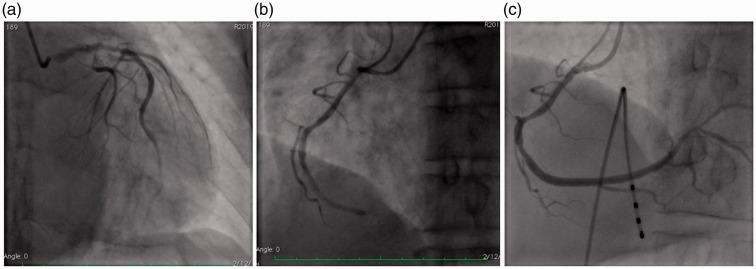

The complication of myocardial infarction after using intravenous recombinant tissue plasminogen activator (rt-PA) in patients with acute ischemic stroke is rare. Several of these cases have been reported in the first 3 hours after infusion of rt-PA. There is controversy on how to manage treatment of the coronary artery, such as intravenous anticoagulants and antiplatelets, at the same time. We introduce a new strategy for treatment of a patient who had ischemic stroke and developed myocardial infarction after intravenous rt-PA therapy. Our case had coronary and cerebral intervention in combination with low-dose intravenous rt-PA. He was successfully treated for coronary occlusion with aspiration thrombectomy.

急性缺血性卒中患者静脉注射重组组织型纤溶酶原激活剂(rt-PA)后发生心肌梗死的并发症较为罕见。其中几例病例已在输注rt-PA后的最初3小时内被报道。对于如何同时处理冠状动脉的治疗,如静脉抗凝和抗血小板治疗,存在争议。我们介绍一种治疗策略,用于一名在静脉注射rt-PA治疗后发生缺血性卒中和心肌梗死的患者。我们的病例采用冠状动脉和脑血管介入联合小剂量静脉rt-PA治疗。他通过血栓抽吸术成功治疗了冠状动脉闭塞。